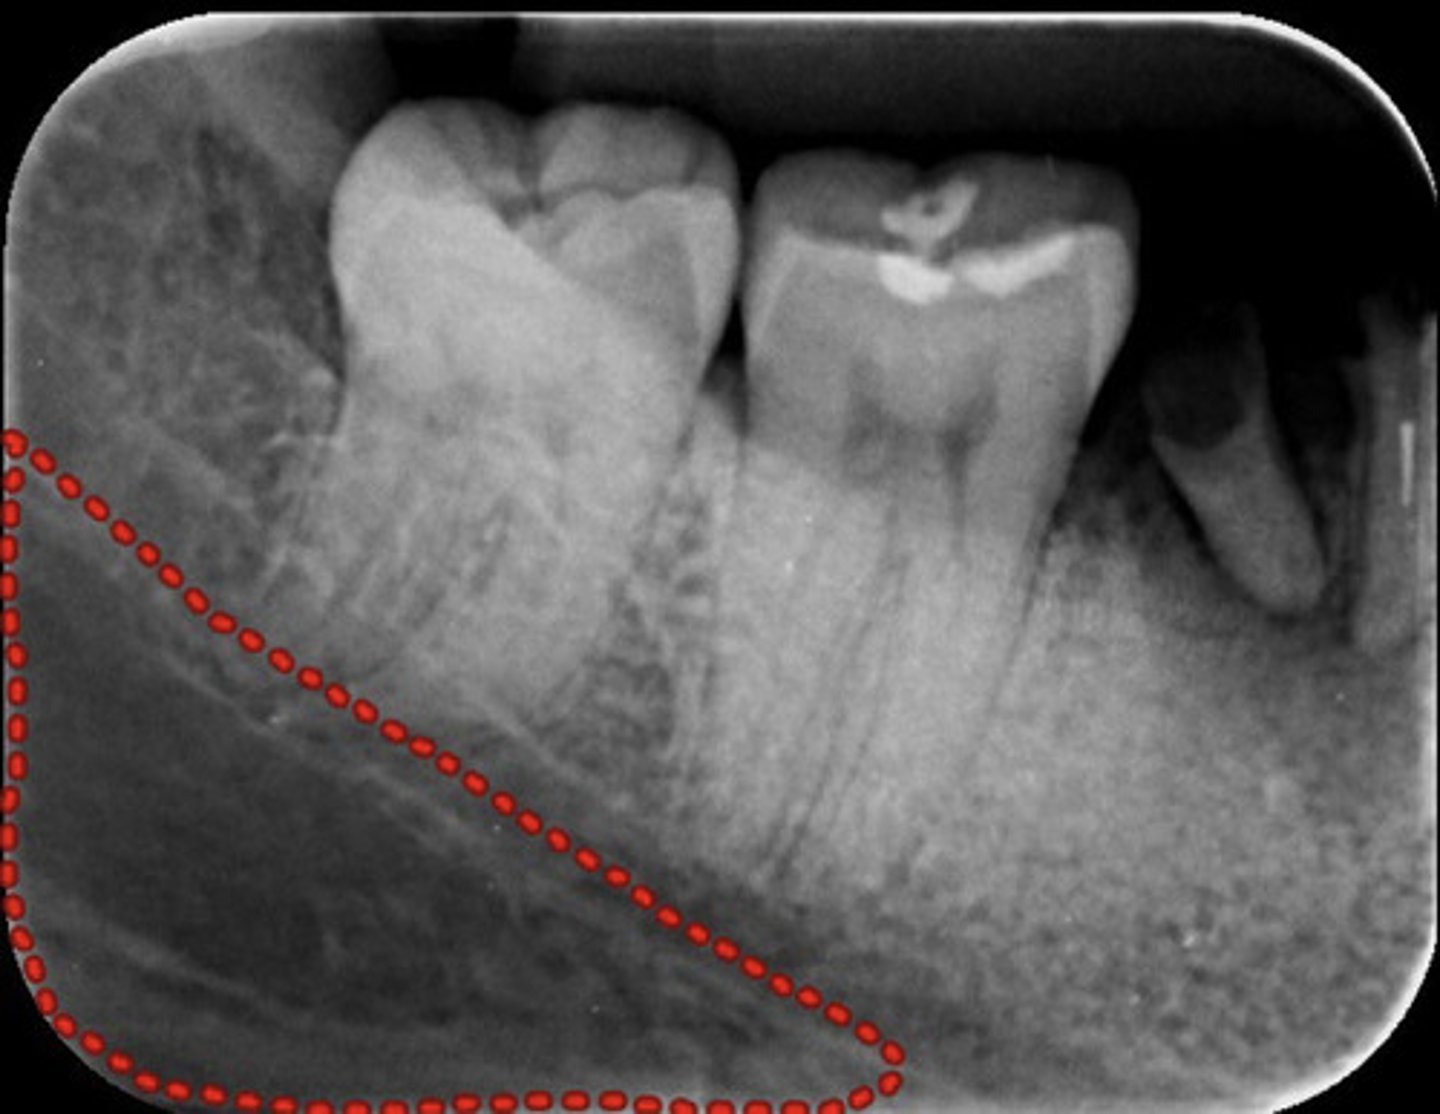

What does the mandibular canal look like radiographically?

information on mandibular canal

radioluncentt band, with two thin radiopaque line & below the apices of the mandibular molar teeth

What can be viewed from a projection of the posterior molars? (start at coronal portion and work toward apex)

coronal

1. external oblique

2. Inferior oblique (mylohyoid ridge)

3. mandibular canal

4. mandibular gland fossa

5. inferior border of mandible

What is the submandibular gland fossa?

information on submandibular gland fossa

radiolucent area in the molar region below the mylohyoid ridge